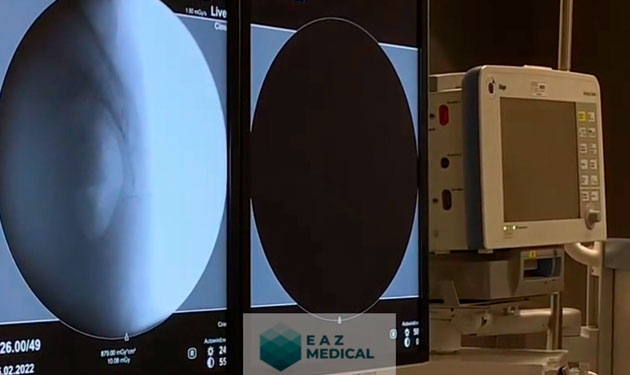

Radiofrecuencia en tratamiento de hernias discales.

Radiofrecuencia para tratar Radiculopatía lumbar.

Radiofrecuencia en tratamiento de Neuralgía del Trigémino

Tratamiento de hernias cervicales